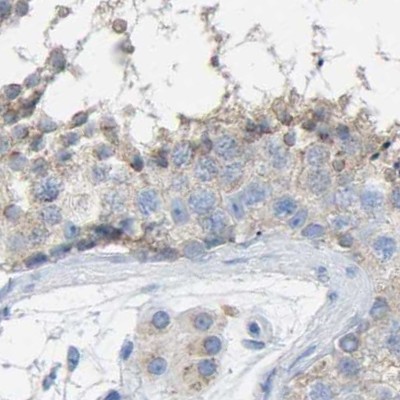

Immunohistochemistry analysis in human skin and skeletal muscle tissues using HPA019025 antibody. Corresponding SERPINB5 RNA-seq data are presented for the same tissues.